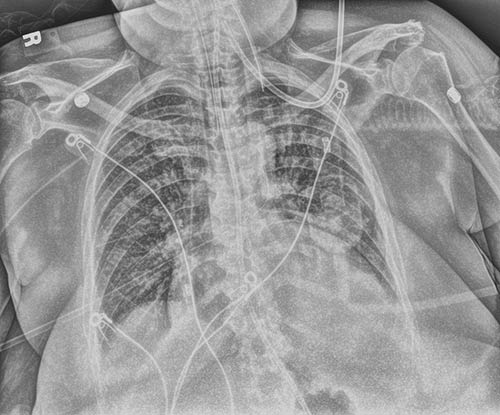

Tenga más seguridad con una exposición única. La mejora de tubos y catéteres crea una imagen guía y utiliza un procesamiento optimizado para una visualización más clara y sencilla de tubos y catéteres de PICC. Aumenta la confianza de que las sondas y las vías se han colocado correctamente y permanecen en su lugar.

Modificado

Original